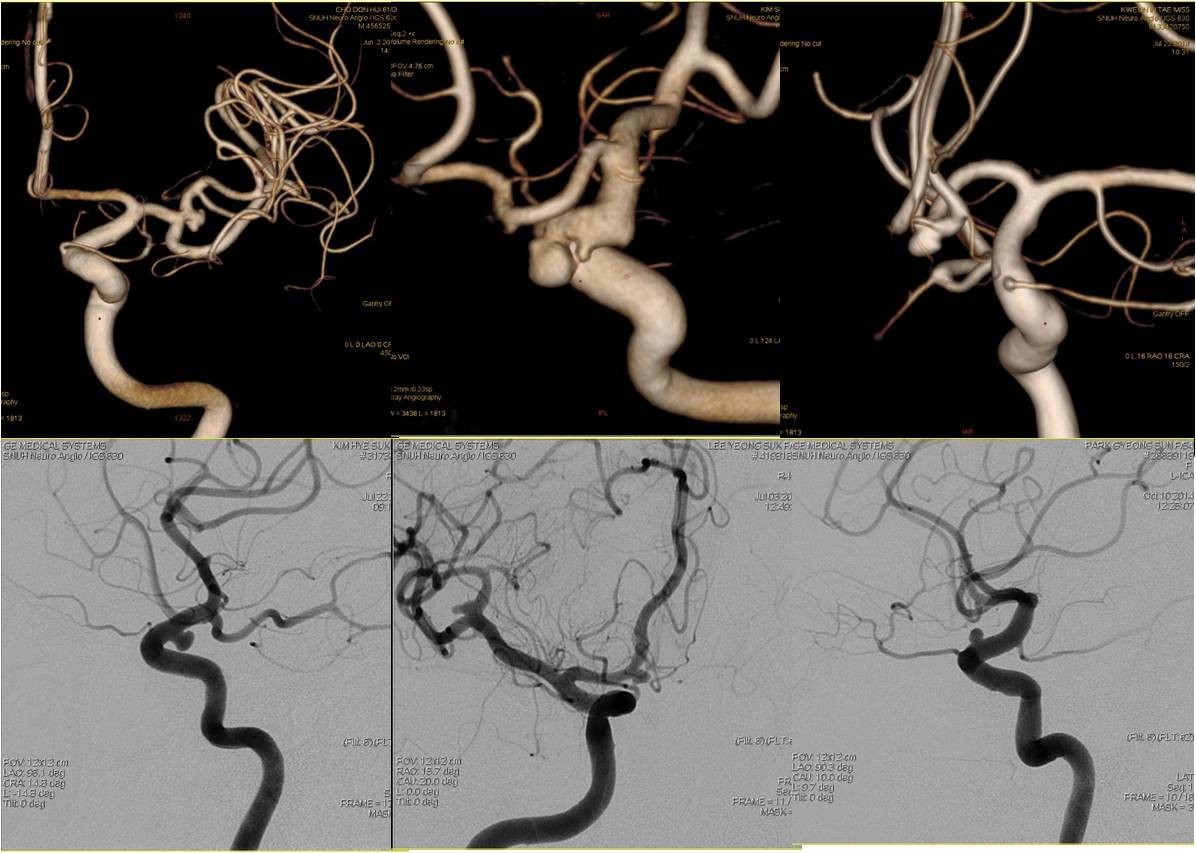

(二)颅内动脉瘤栓塞术

病例1:前交通动脉动脉瘤(Acom-An)

》男性,40岁,因头痛6个月、加重1天入院,头痛为全脑胀痛,疼痛较剧烈,为求进一步诊治就诊于我院门诊,按“头痛待查”收入我院。

》入院时查体:神经系统查体未见阳性定位体征。

》入院后行头颅MRA发现前交通动脉囊状动脉瘤。

病例2:后交通动脉动脉瘤(Pcom-An)

》女性,59岁,因一过性意识不清伴头痛20天入院,头痛为全头炸裂样疼痛,于当地医院检查后诊断为“蛛网膜下腔出血”保守治疗20天,现仍有头痛,为求进一步诊治入院。既往有高血压病病史40年,血压控制不详。

》入院时查体:项强3横指。

术前、术后DSA对比

》DSA检查发现右侧后交通动脉动脉瘤,全麻下行颅内动脉瘤栓塞术。

病例3:后交通动脉未破裂动脉瘤栓塞

》女性,23岁,因间断头痛、头晕6个月,加重2天入院,头痛全脑胀痛,不伴有恶心、呕吐,无耳鸣及听力减退,行头颅CT后按“头痛待查”收入我科。